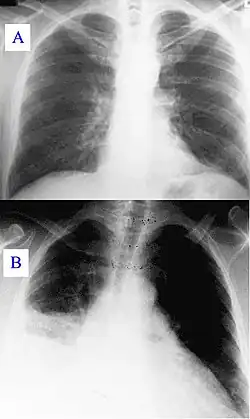

Im Verlauf der Erkrankung kann eine Lungenentzündung (atypische Pneumonie) auftreten, welche in einem lebensbedrohlichen akuten Atemnot-Syndrom (ARDS) resultieren kann. Etwaige atmungsbedingte Symptome treten gewöhnlich früh auf (4–5 Tage nach Beginn der Erkrankung).

Bei Fieber unklarer Ursache kommt Q-Fieber differentialdiagnostisch in Frage. Ein Röntgenbild der Lunge kann zur Diagnose führen.